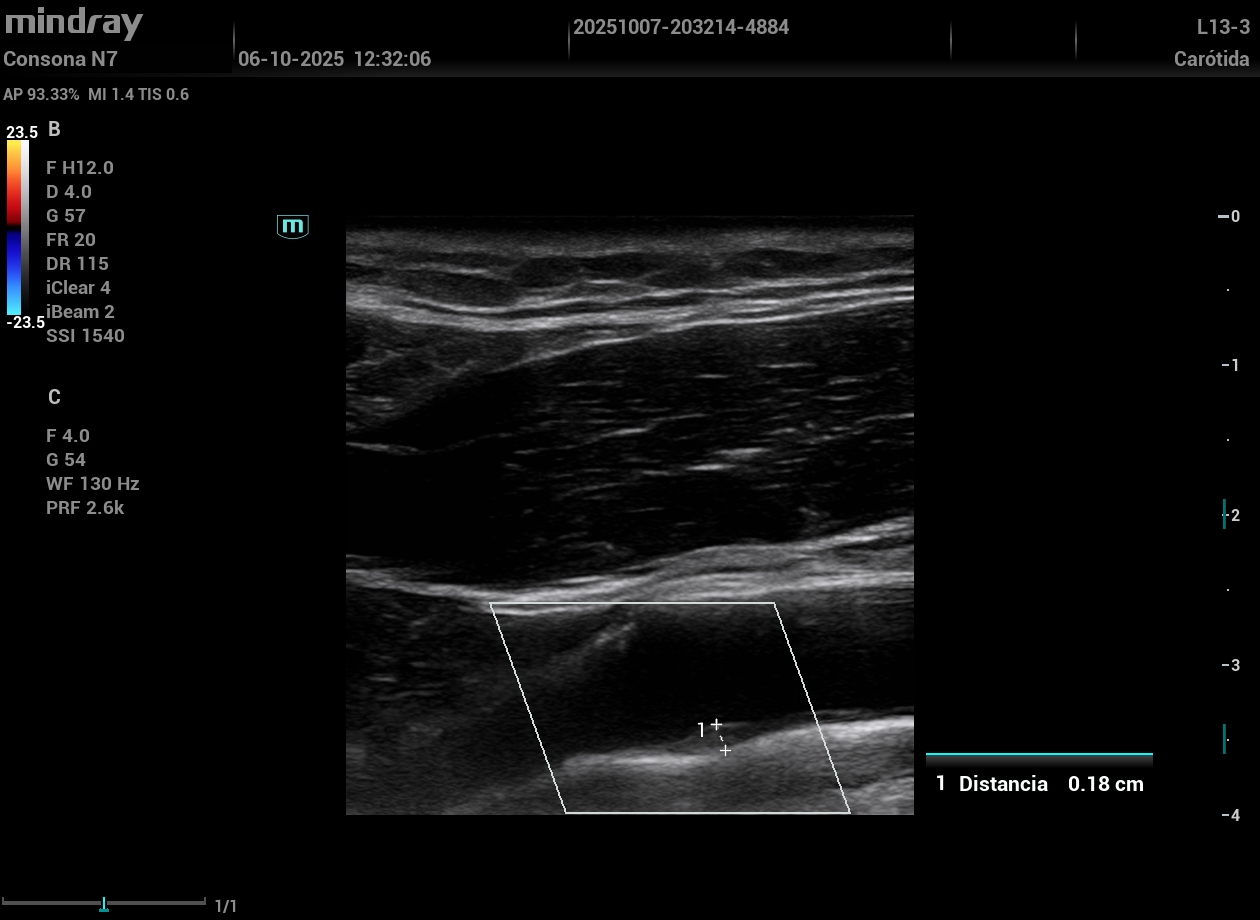

Implementar la ecografía Doppler de arterias carótidas y femorales como herramienta diagnóstica complementaria.

Inspirada por la rotación de una tutora en la Unidad de Riesgo Cardiovascular de un hospital, se formó al equipo en ecografía vascular e incorporó la técnica a la consulta. Se evaluó a 17 varones (50–65 años) que consultaron por disfunción eréctil sin enfermedad cardiovascular conocida y con RCV bajo-moderado por SCORE2. Se realizó una ecografía vascular aplicando el protocolo VASUS (arterias carótidas, femorales y aorta), identificando placas ateroscleróticas no detectadas antes. Estos hallazgos motivaron intensificar cambios en el estilo de vida, estrechar el seguimiento y ajustar tratamiento farmacológico.